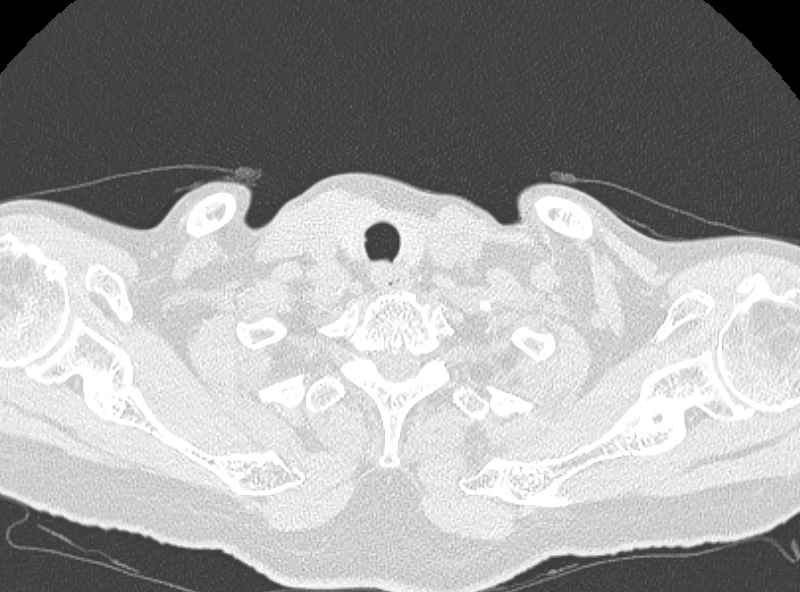

昨天值班遇到的一例晕厥病例,差点漏诊,而最终的解法,始于最简单而质朴的查体。国庆中秋双节的最后一天,8号的早上8点,抢救室床旁晨交班,病人依旧是多而重,交到6床,一个刚入室不久的病人,准备去做CT,夜班医师汇报病史:69岁男性,本次因“头晕伴一过性晕厥1小时”为主诉入抢,1小时前于高铁站因即将赶不上高铁走路快时突发头晕,伴一过性晕厥,约3-4分钟后清醒,清醒后诉今晨未吃早餐,已服用降压药物,仍有头晕头痛、四肢乏力等不适,无胸闷胸痛,无畏寒发热,无咳嗽咳痰,无恶心呕吐,无肢体麻木,无视物模糊等不适,路人拨打120送至我院急诊就诊。既往高血压,长期服用氨氯地平+福辛普利,血压控制一般;糖尿病,长期